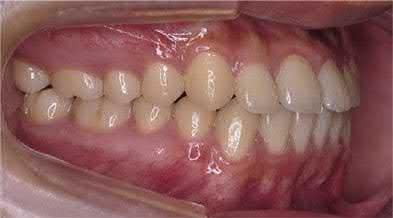

1.1  Class III correction with TADs and sliding jigs [7]. (a) Initial examination indicated full-step Class III canine and molar relationships. (b) TADs were placed and connected with a sliding jig. (c) Schematic illustration shows a miniscrew-anchored sliding jig and the direction of the force. (d) Final examination indicated Class I canine and molar relationships. Source: Tai et al. [7]. Reprinted with permission from Elsevier.

(a)

(b)

(d)

(c)

Figure